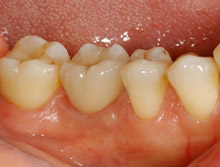

下顎大臼歯部のインプラント

この症例は、保存が困難な第一大臼歯をインプラントで治療した例です。

治療前

アバットメントの装着後

8年後